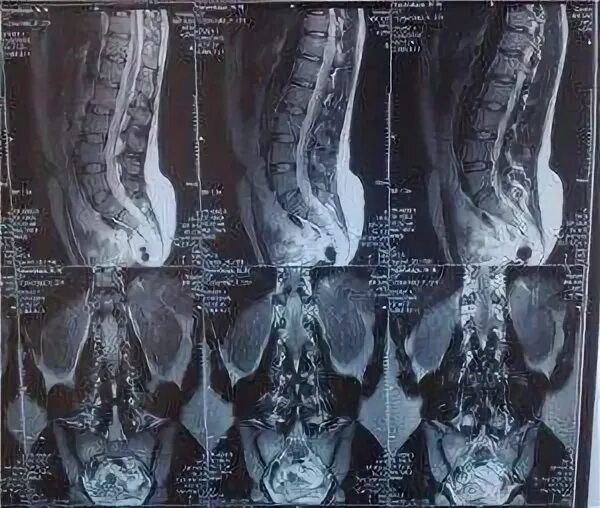

Протрузия l1 l2 l4 l5